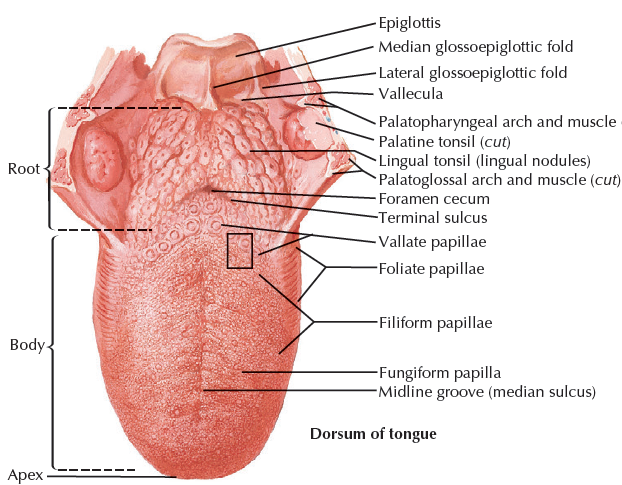

舌頭

Structure

- Terminal sulcus(terminalis)分前後

Papillae

Filiform

- 最多

- 無 taste buds

Fungiform

- 前側

- CN VII

Foliate

Circumvallate

- 後側

- CN IX

Nerve

運動

感覺

- 根部 taste/ general sense

- 後 taste/ general sense

- 前

- Taste: Chorda tympanic

- General sense: Lingual n